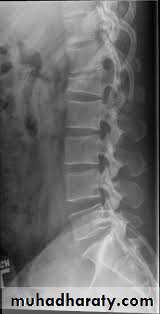

Plain x ray

Compression( wedge ) fracture

45% of TL#sFailure of anterior column

The middle column is intact and acts as a hinge.

Low risk of Neurological deficits .